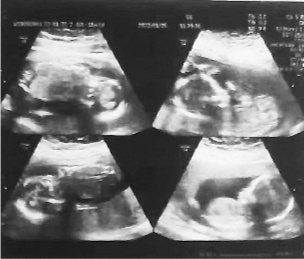

超声报告。

近日,山东济宁一位孕妇潘潘(化名)分3次生下四胞胎男孩备受关注。

3月22日,老大在孕25周6天的时候出生,体重735克。4天后,老二出生,重870克。4月1日,老三老四出生,一个1050克,一个1030克。